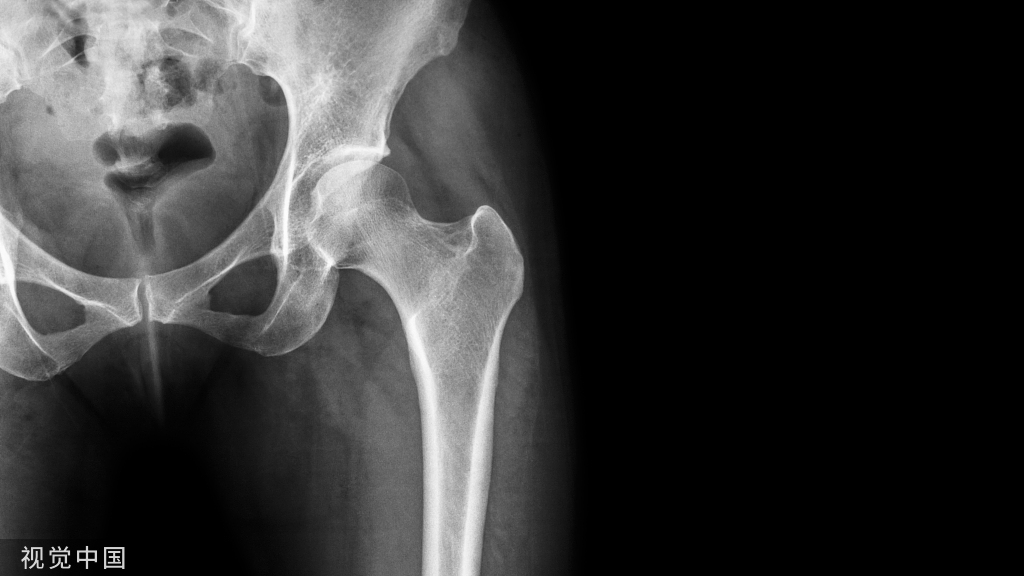

2.经骨折线作一线与上述轴线相交;3.相交后形成夹角,辨认出锐角处;

图2 胫骨近端骨折同理。